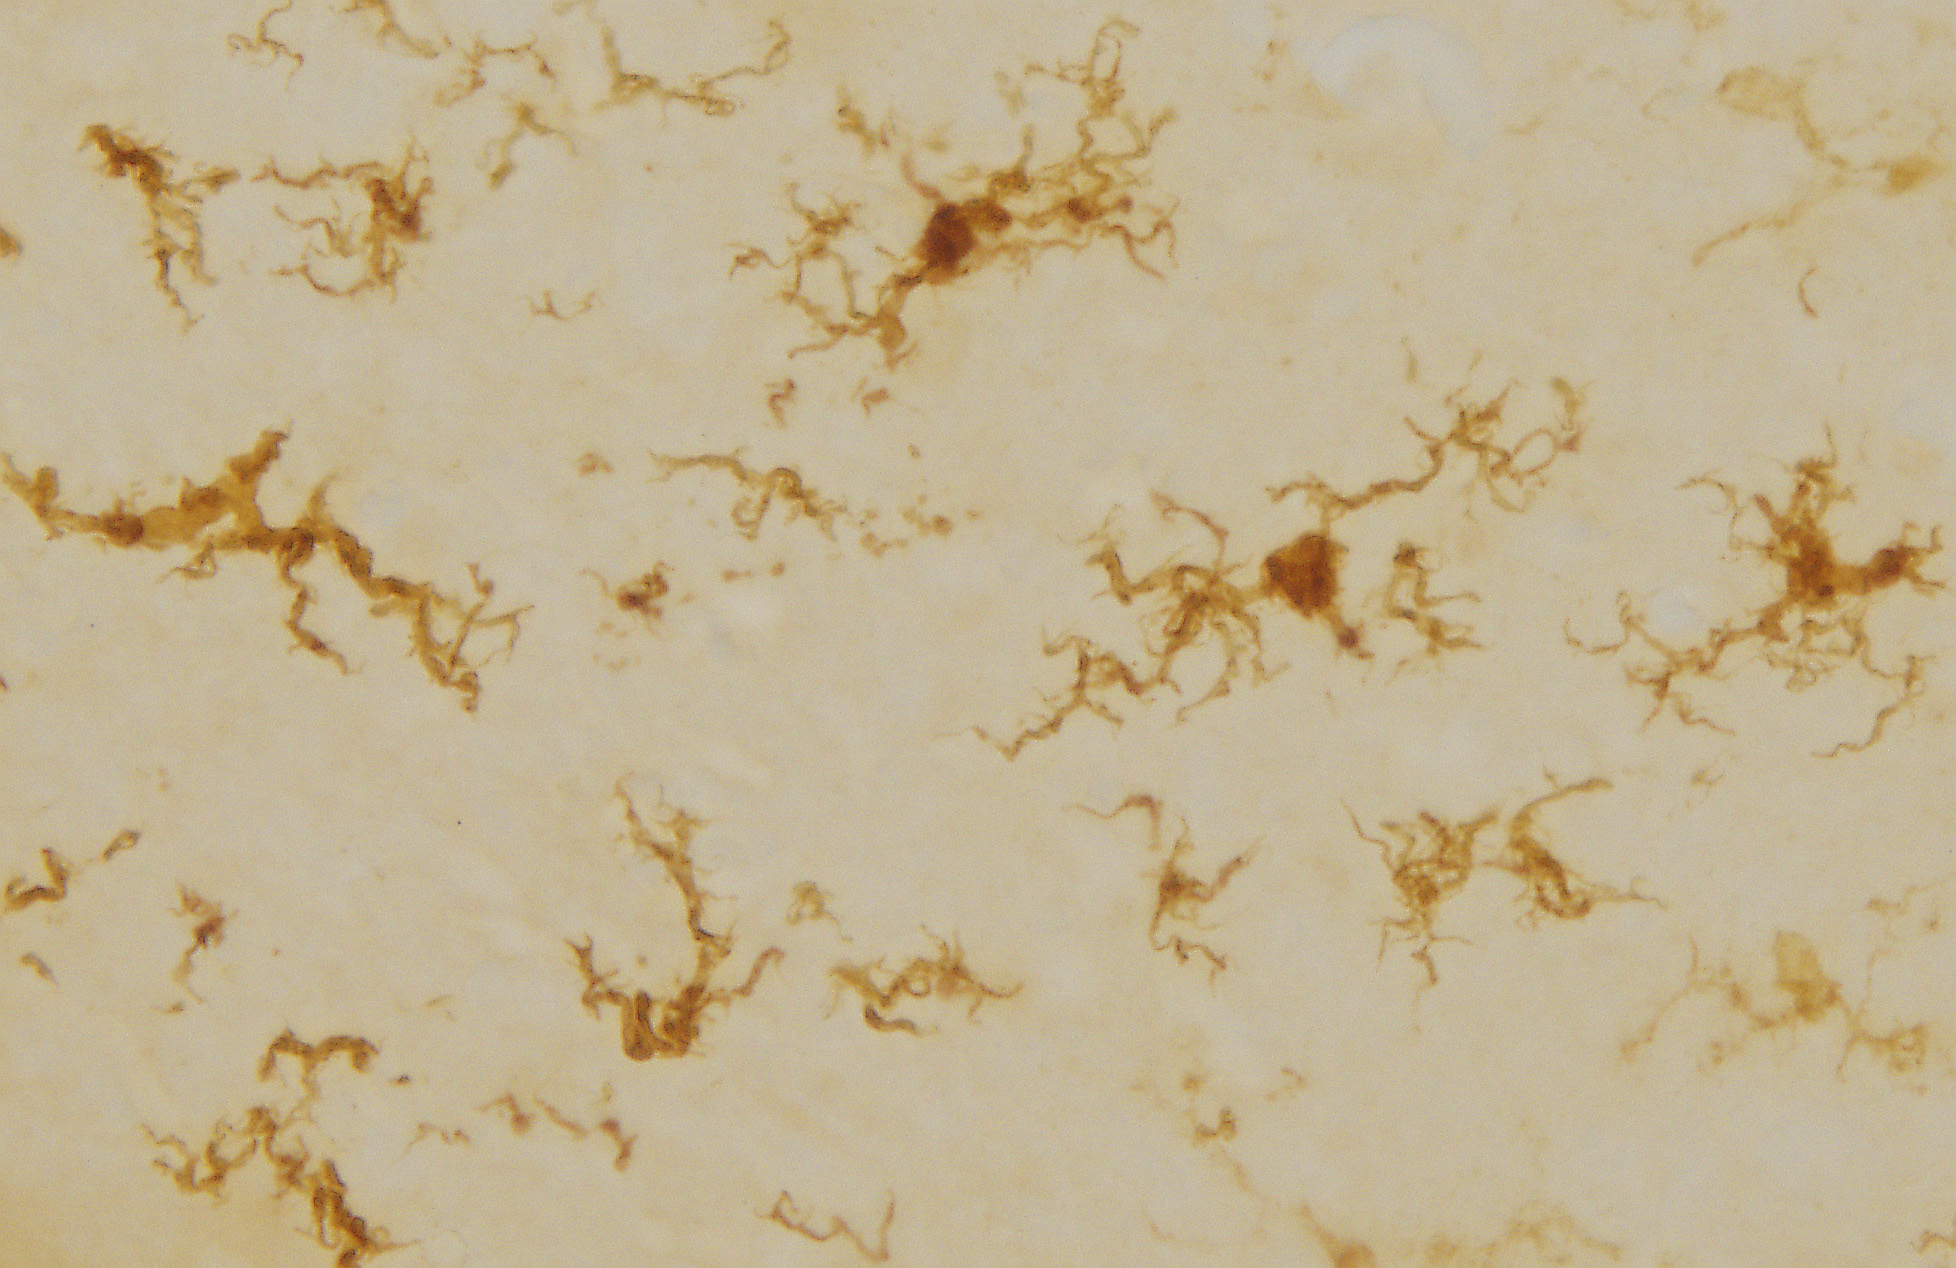

Gold beats platinum for chemo drugs in new lab study

Gold-based drugs can slow tumour growth in animals by 82% and target cancers more selectively than standard chemotherapy drugs, according to new research out of RMIT University.